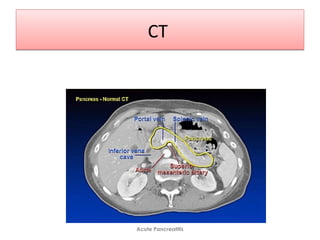

Computed TomographyComputed Tomography

• Abdominal CT is not indicated for patients with mild pancreatitis.

• Always indicated in severe AP and is the imaging study of choice for assessing

complications.

• Scans done after > 72 hours after symptom onset unless the diagnosis is

uncertain, because inflammatory changes are often not radiographically present

until this time.

• Abdominal CT scans also provide prognostic information based on the

following grading scale developed by Balthazar & colleagues.

• Grade A - Normal pancreas

• Grade B - Focal or diffuse gland enlargement

• Grade C - Intrinsic gland abnormality recognized by haziness on the scan

• Grade D - Single ill-defined collection or phlegmon

• Grade E - Two or more ill-defined collections or the presence of gas in

or nearby the pancreas

Normal PancreasNormal Pancreas